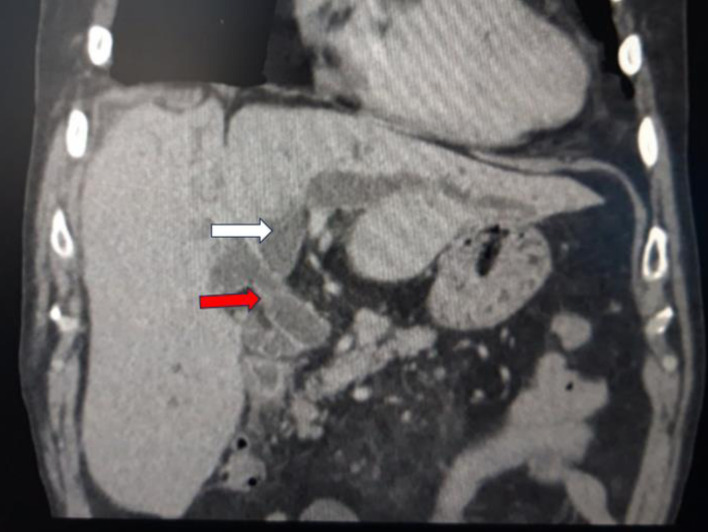

Endoscopic retrograde cholangiopancreatography (ERCP) is an important technique for treating biliary obstruction. A case report of a 75-year-old male with diagnosed choledocholithiasis and cholangitis was presented. He had a history of hepatic surgery 45 years ago, and during the ERCP, an unusual clinical scenario was encountered. Retained extraction basket during ERCP is a rare but known complication and there are no standard recommendations to manage it. To our knowledge, this is the first case report described in the literature with retention of an extraction basket in surgical sutures at ERCP and the longest period from surgery to stone formation in the biliary system. This case report aims to emphasize that in patients with a history of hepatobiliary surgery, postoperative material can cause complications during ERCP.